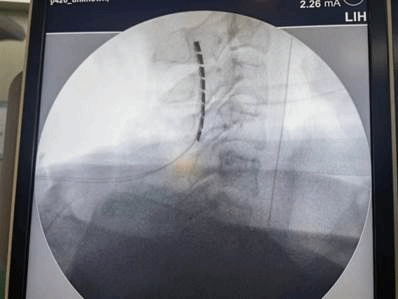

手术中骨科刘晓东副主任医师用C臂机定位电极植入位置

脊髓电刺激作为一种新型有效的植物人促醒技术,通过在高位颈髓植入电极,脉冲式放电由脊髓传入大脑,增加大脑血流量,激活神经系统,改善脑循环,兴奋大脑皮层,达到促醒的目的。经过缜密的术前准备,郭冕教授带领团队成功将刺激电极安置在患者颈2-4硬脊膜外,以增强脑干网状激活系统起始部意识冲动的输入,实现促醒。手术一周后顺利开机,目前宋先生电刺激反应良好,意识状态得到显著的改善。